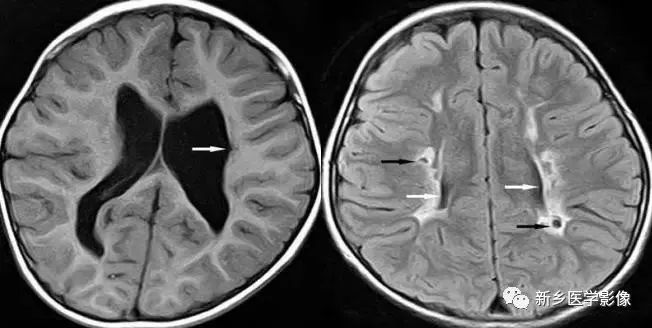

❺ 脑室周围白质软化症

主要与缺血缺氧及感染有关。常见于早产儿,是造成早产儿脑瘫的主要原因。

由于脑室周围白质的血供分别来自脑室区和远脑室区的终动脉,未成熟儿终动脉深穿支的侧支循环尚未建立,而胚胎晚期脑室周围白质对缺血缺氧敏感,所以,脑室周围自质软化症多见于早产儿。

由于病灶常为双侧性,故双侧侧脑室多同时扩大。脑白质内软化灶在CT扫描时表现为白质内斑片状低密度灶,MR上T1加权图呈低信号,T2加权图呈高信号。